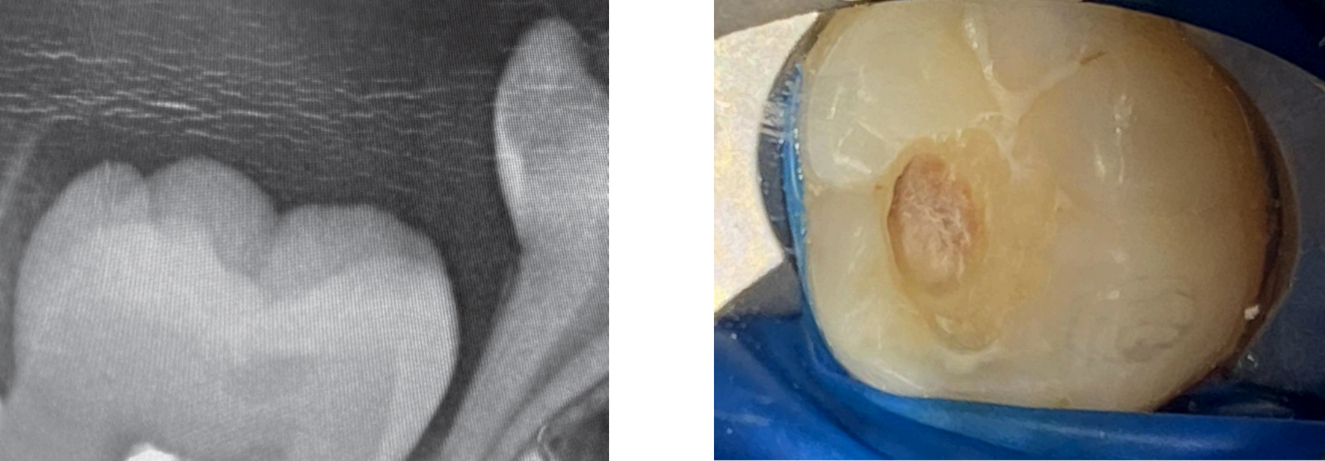

Термин внутрикоронковая резорбция до прорезывания описывает форму резорбции твердых тканей зуба, начинающуюся до прорезывания и затрагивающую внутренние структуры полностью сформированной коронки еще непрорезавшегося зуба (рис. 1a–b).

Рис. 1. а: На прицельной (bitewing) рентгенограмме выявлен внутрикоронковый дефект в непрорезавшемся первом моляре нижней челюсти справа у 6-летней девочки, при отсутствии каких-либо клинических признаков кариеса. б: После прорезывания витальный и бессимптомный моляр был восстановлен композитной пломбой после удаления грануляционной ткани, без обнажения пульпы. На момент лечения пациентке было 7,5 лет.